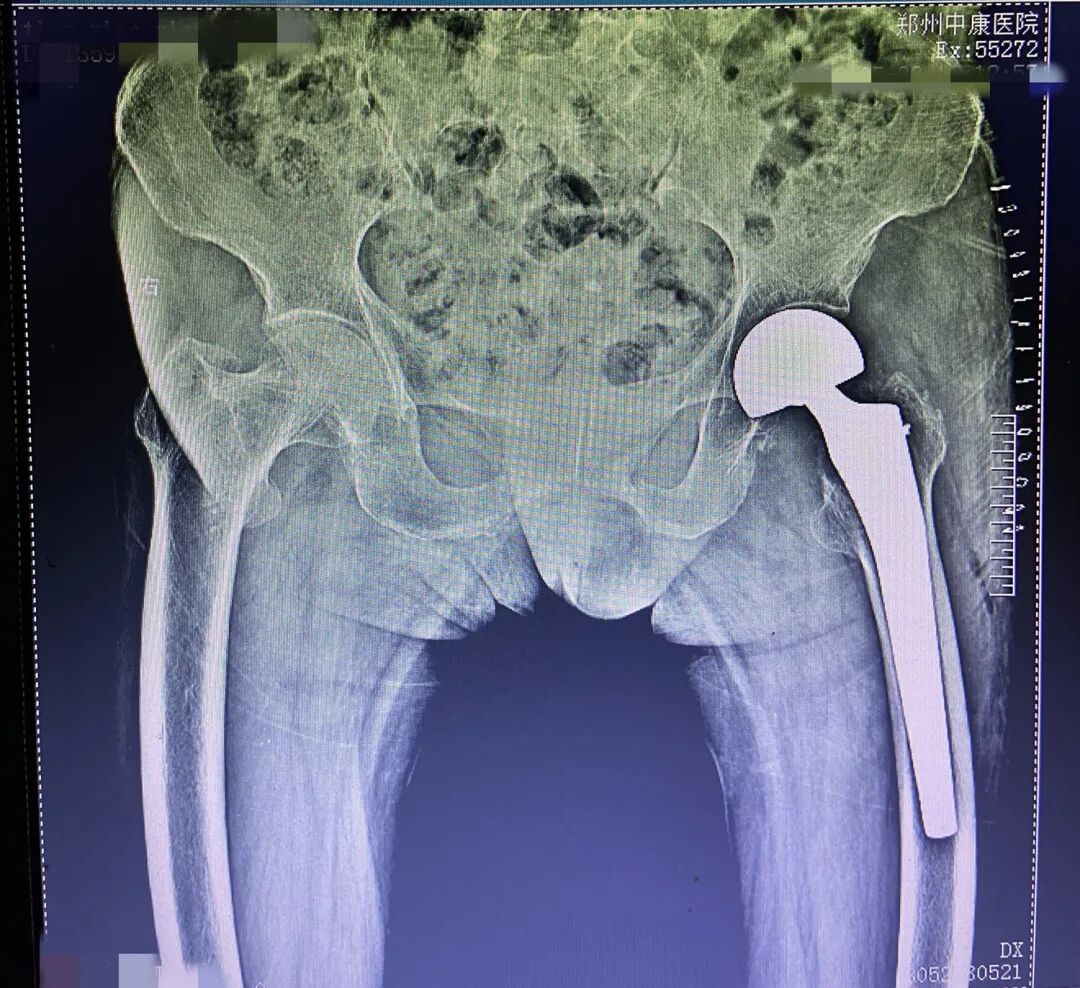

近日,家住岳村镇张楼沟村,65岁的田某在中康医院进行了髋关节置换手术。

人工髋关节由30000元左右降至9000元左右,个人负担大幅降低。这正是得益于第二批国家组织高值医用耗材——人工关节的集中带量采购结果在我省落地。